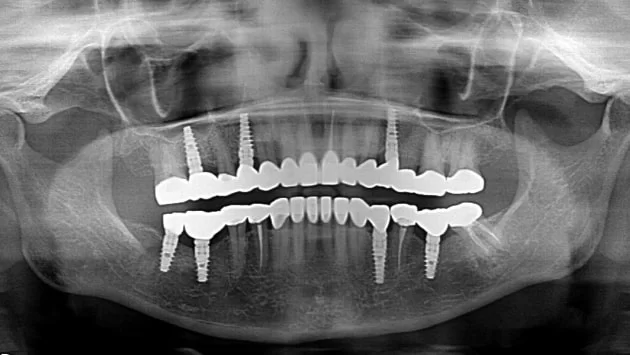

El tratamiento All on 4 es una técnica patentada que utiliza solo cuatro implantes para una restauración dental completa. Con este procedimiento obtienes dientes firmes, funcionales y con una apariencia impecable. Mejora de inmediato tu forma de comer, hablar y sonreír.